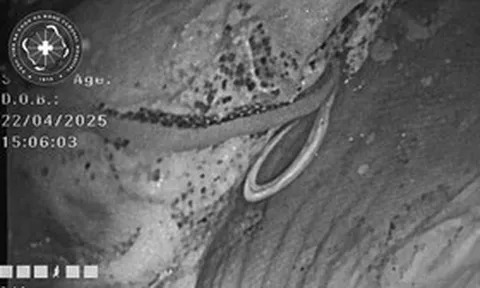

Người đàn ông 62 tuổi tử vong vì suy thận giai đoạn cuối. Ảnh minh họa.